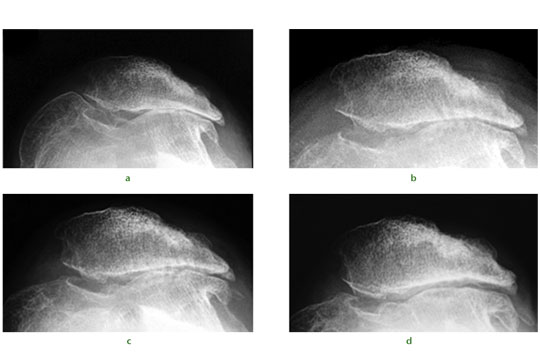

Fig. 1 A 34-year-old female presented with recurrent dislocation of her patella as an adolescent. Radiographs were taken a) pre-operatively, and b) immediately post-operatively showing evidence of subchondral drilling. Radiographs at c) six months and d) two years showed a progressive reappearance of the lateral patellofemoral articulation.

We have published some early results of stem cell therapy for osteochondral defects. A typical case would be that of a 34-year-old ex-orthopaedic nurse presenting following multiple previous operations for patellar dislocation and complete loss of the lateral patellofemoral articular facet cartilage (Fig.1a). Rather than a total knee replacement she underwent arthroscopic debridement, lateral patellar release, and subchondral drilling. Intra-operative findings were of multiple grade III and IV lesions over the entire patellofemoral joint. The traditional surgical approach of osteophyte removal and subchondral drilling over the entire patellofemoral joint (Fig.1b) was performed and supplemented with intra-articular injections of PBSC with HA. Over the following two years, radiographs illustrate progressive reappearance of the lateral patellofemoral joint space (Figs 1c and 1d). At two years after surgery, the patellofemoral crepitation was minimal and the knee function gradually improved.5